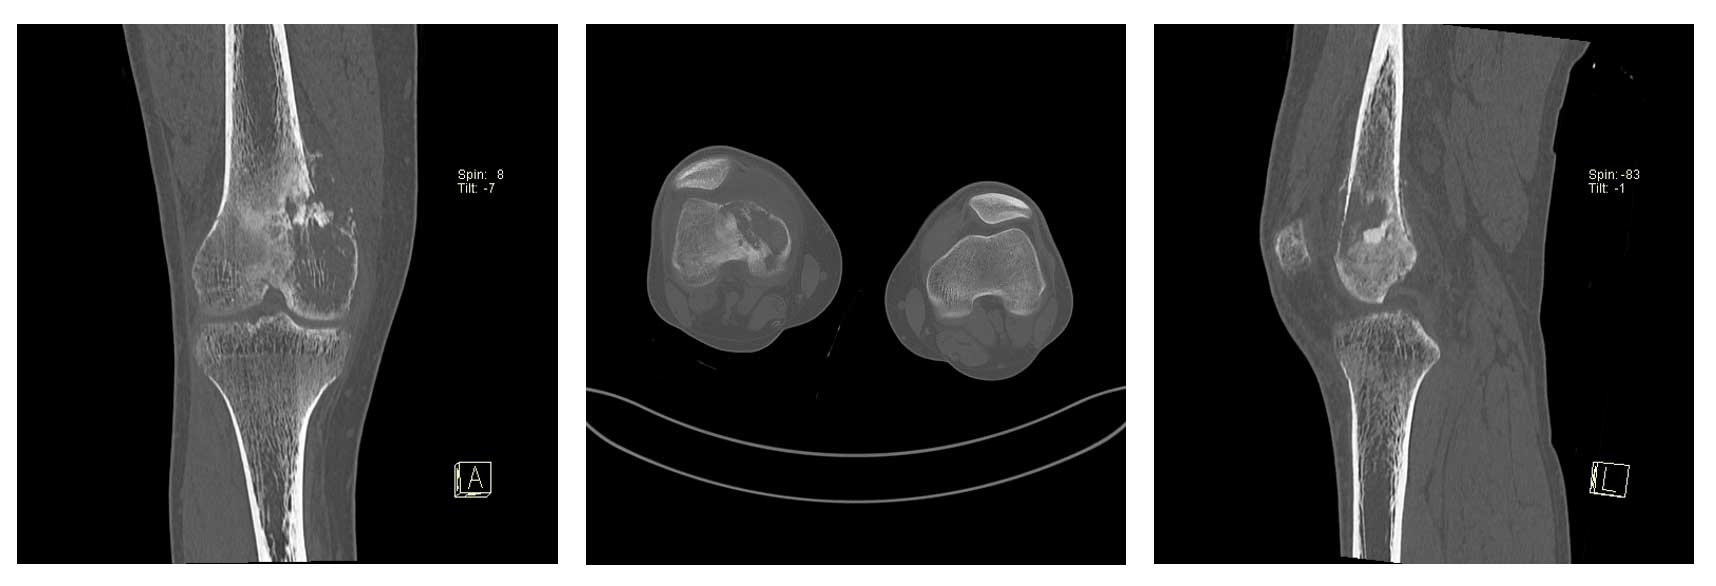

Ameliyat Öncesi: Tomografide kemik yıkımı daha ayrıntılı görülmekte.